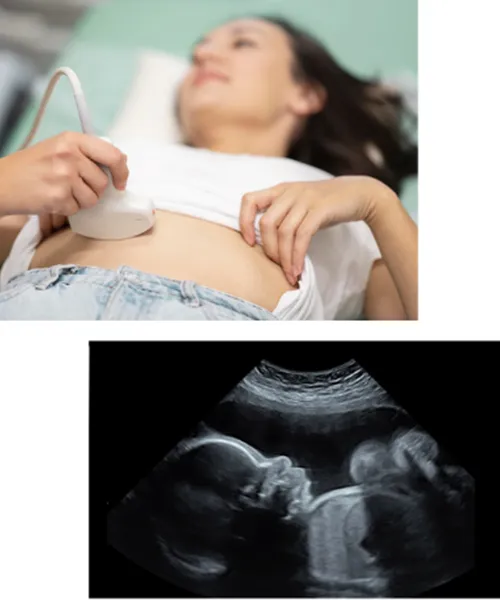

Viability scan

Anomaly Scan